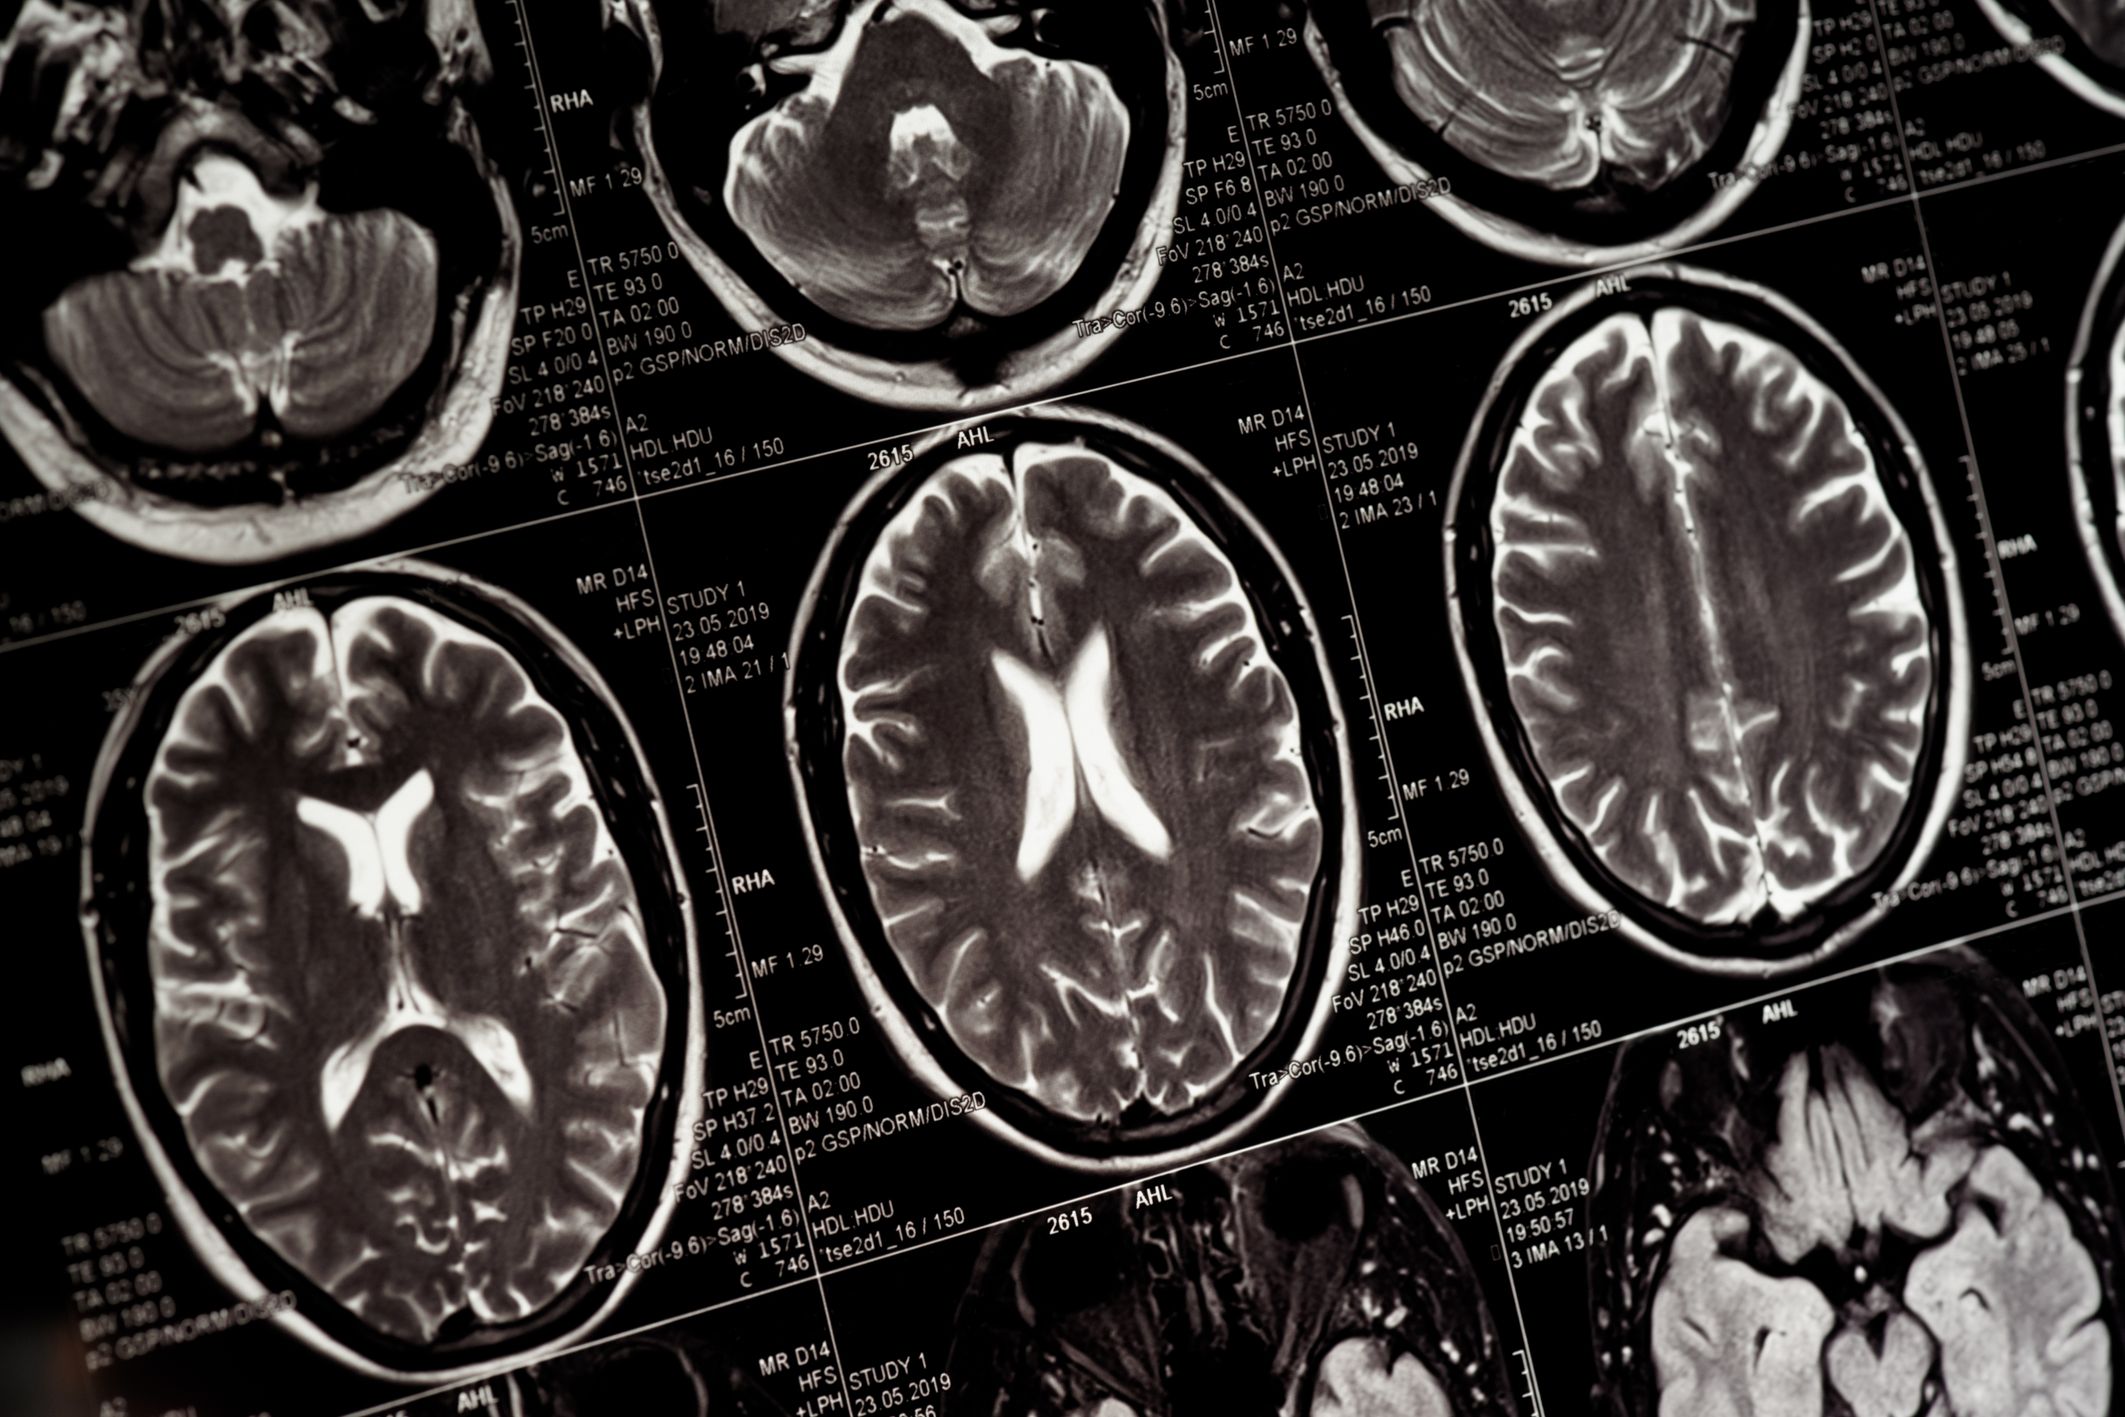

นักอ่านผลแล็บ AI ช่วยแพทย์อ่านผลตรวจ MRI สมองได้ในเวลาเพียงไม่กี่วินาที ซึ่งให้ผลลัพธ์ที่แม่นยำ ทำให้แพทย์สามารถวางแผนการรักษาได้ไวขึ้น

ในนาทีวิกฤตของผู้ป่วยโรคสมอง ทุกวินาทีคือตัวตัดสินโอกาสรอดชีวิต ล่าสุดนักวิทยาศาสตร์ได้พัฒนาเทคโนโลยีปัญญาประดิษฐ์อัจฉริยะนามว่า "PRIMA" ที่สามารถวิเคราะห์ภาพสแกน MRI ได้ในเสี้ยววินาที โดยให้ผลลัพธ์ที่แม่นยำและครอบคลุม ช่วยให้แพทย์วินิจฉัยโรคซับซ้อนได้ทันท่วงที และลดระยะเวลาการรอผลตรวจนานหลายชั่วโมงให้สั้นลง

ทีมนักวิจัยและศัลยแพทย์ประสาทจาก มหาวิทยาลัยมิชิแกน (University of Michigan) สถาบันการแพทย์ชั้นนำของประเทศสหรัฐอเมริกา ได้เผยแพร่โมเดลปัญญาประดิษฐ์ที่มีชื่อว่า PRIMA (Promptable Radiology Intelligent Medical Assistant) ในวารสารวิชาการ Nature Biomedical Engineering โดยทีมวิจัยได้พัฒนาระบบ PRIMA ให้ทำหน้าที่เป็น "ผู้ช่วยรังสีแพทย์อัจฉริยะ" ที่เป็นเสมือน “นักอ่านผลแล็บ” โดยช่วยอ่านและประมวลผลภาพถ่ายทางรังสีของสมอง (MRI)